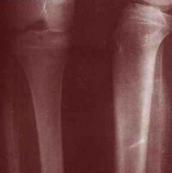

骨外尤文氏瘤

疾病介绍:骨外尤文氏瘤是组织学上同骨尤文氏瘤一样,而发生于软组织中的肿瘤。多见于青壮年,85%在20~30岁,男女发病率相近,发生部位多数见于四肢及...[详细]